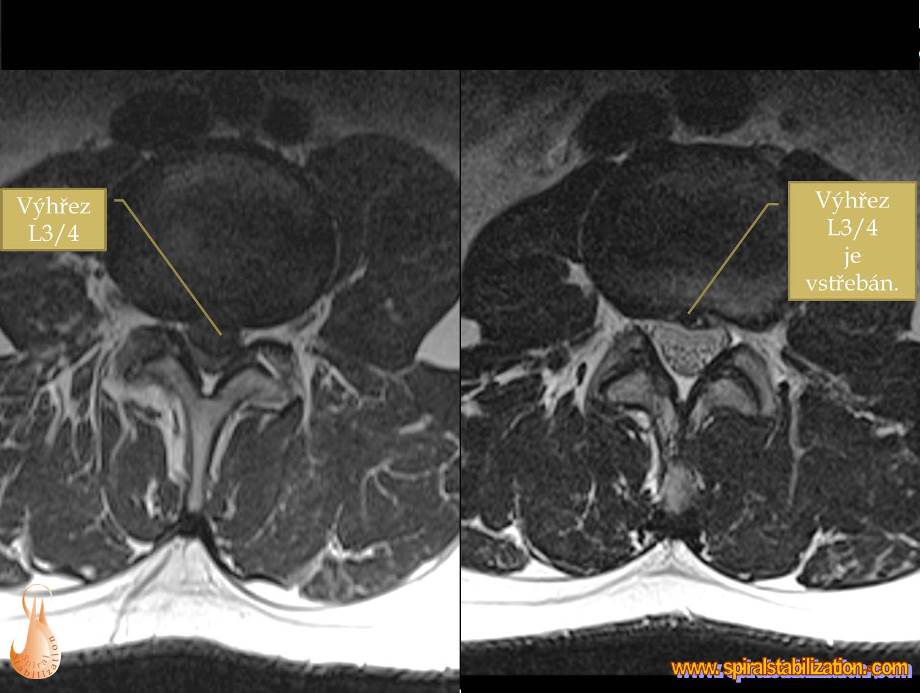

Výsledky hernia L3/L4